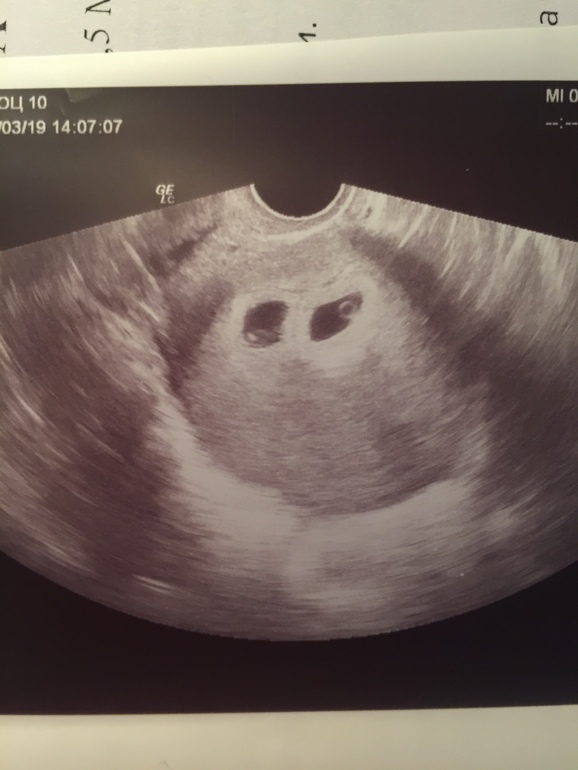

Второе узи 9-я неделя

УЗИ, КТГ, доплер, скрининг, ХГЧ и другие анализыНе утерпела, хотелось сердцебиение послушать. На 7-ой неделе не слышали, и эмбрионов ещё не видно было. Да и Папа захотел посмотреть. Сегодня сходили на Узи в другое место. Подросли малыши) абсолютно одинаковые, по 14 мм. И ПЯ по 27 мм. Дихориальные. Сердечко послушали, 166 и 171. Эх, хотелось бы верить в теорию, что у мальчиков до 150, а у девочек выше) Ну время покажет.

Единственное что, мне показалось, УЗи аппарат не такой четкий и чувствительный, чем первый был? Вот сравните, в первый раз на 7 неделе врач и я прямо сразу увидели два одинаковых ПЯ. А сейчас крутила вертела и плохо видно было. Или это просто из-за срока беременности так? Сказала они друг над другом и поэтому второй плохо видно. Смотрите, первое и второе УЗИ: